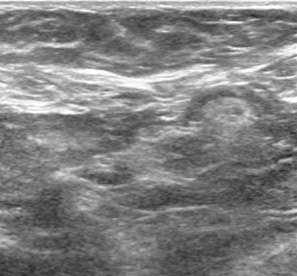

Ultrasound is the primary imaging modality used in the evaluation of lumps outside of the breast or in patients who are less than 30 years of age.2 On ultrasound, accessory breast tissue appears like breast tissue within the main pectoral breast – a mixture of fibroglandular tissue and lobules of fat (Fig. 2).